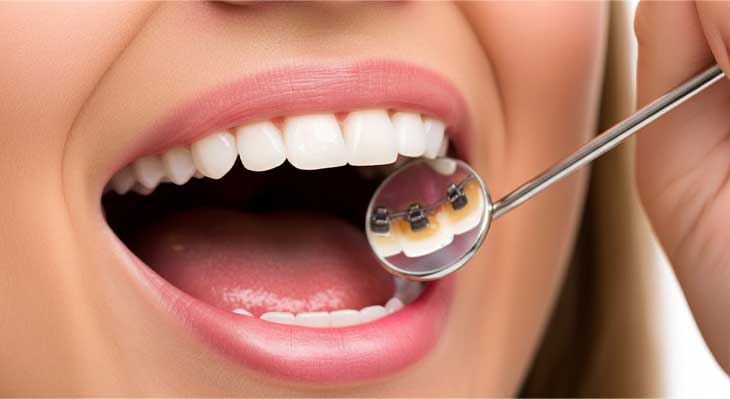

ارتودنسی لینگوال که به آن ارتودنسی پشت دندانی یا مخفی نیز گفته می شود، پیشرفته ترین و پنهان ترین روش در میان سیستم های ارتودنسی ثابت است. در این تکنیک منحصر به فرد، تمام اجزای دستگاه ارتودنسی، شامل براکت ها و سیم ها، به جای سطح بیرونی، بر روی سطح داخلی (زبانی) دندان ها نصب می شوند. این ویژگی باعث می شود که دستگاه از بیرون کاملا غیر قابل مشاهده باشد و بیمار بتواند بدون هیچگونه نگرانی از بابت ظاهر خود، دوره درمان را سپری کند. این روش یک گزینه ایده آل برای بزرگسالان، افراد مشهور و تمام کسانی است که به دنبال دستیابی به یک لبخند زیبا بدون دیده شدن بریس های ارتودنسی هستند.

ارتودنسی لینگوال یک روش درمانی کاملا تخصصی است. در این روش از دستگاه های ثابت برای مرتب کردن دندان ها استفاده می شود. تفاوت اصلی و انقلابی این روش در محل قرارگیری دستگاه است. تمام اجزای بریس ارتودنسی به سطح پشتی دندان ها، یعنی سمتی که با زبان در تماس است، چسبانده می شوند. این موقعیت استراتژیک باعث می شود که درمان از دید دیگران کاملا پنهان بماند. هیچکس متوجه نخواهد شد که شما تحت درمان ارتودنسی قرار دارید. این ویژگی، بزرگترین مزیت این سیستم درمانی محسوب می شود.

عملکرد این روش کاملا مشابه بریس های سنتی است. براکت های سفارشی به دندان ها متصل می شوند. سیم ارتودنسی از میان این براکت ها عبور می کند. این سیم با اعمال نیروهای ملایم و مداوم، دندان ها را به تدریج به سمت موقعیت ایده آل خود حرکت می دهد. متخصص ارتودنسی در هر جلسه ویزیت، این سیم ها را تنظیم می کند. این تنظیمات برای ادامه روند حرکت دندان ها ضروری است. این سیستم قادر است پیچیده ترین مشکلات دندانی را نیز با دقت بالایی درمان کند.

به دلیل پیچیدگی های فنی و نیاز به دسترسی دشوارتر، این درمان نیازمند مهارت و تخصص بسیار بالای ارتودنتیست است. براکت های مورد استفاده در این روش نیز معمولا با استفاده از تکنولوژی های دیجیتال و به صورت کاملا سفارشی برای هر دندان بیمار ساخته می شوند. این سفارشی سازی، دقت و کارایی درمان را به حداکثر می رساند. این روش ترکیبی از کارایی بالای بریس ثابت و زیبایی مطلق است.